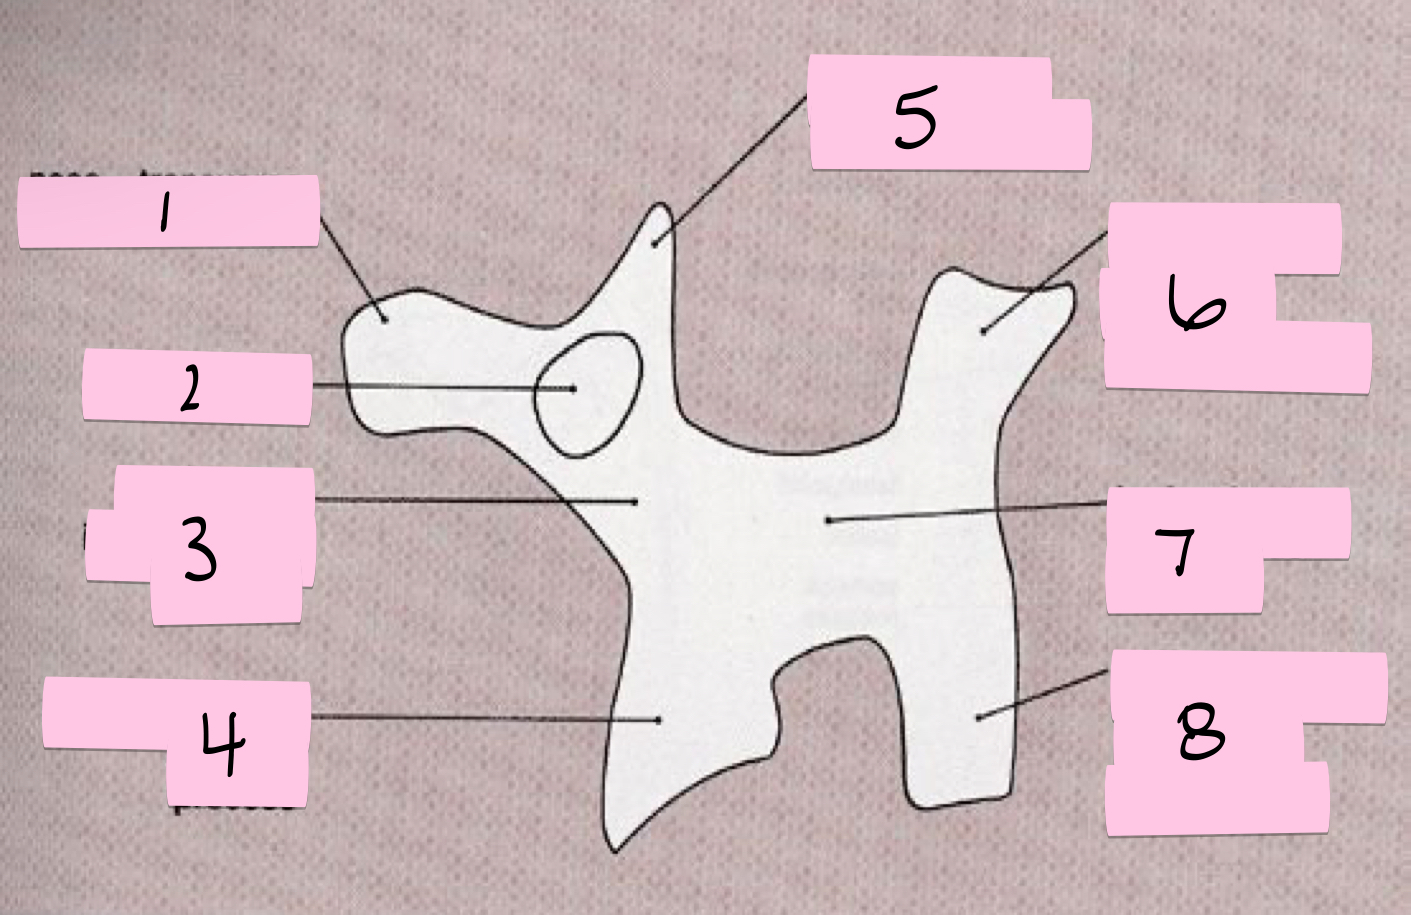

What is 1 pointing to?

Nose- Transverse process

What is 2 pointing to?

Eye- Pedicle

What is 3 pointing to?

Neck- Pars interacticularis (isthmus)

What is 4 pointing to?

Foreleg- Inferior articular process

What is 5 pointing to?

Ear- Superior articular process

What is 6 pointing to?

Tail- Superior articular process of opposite side

What is 7 pointing to?

Body- Lamina and spinous process

What is 8 pointing to?

Hindleg- Inferior articular process of opposite side